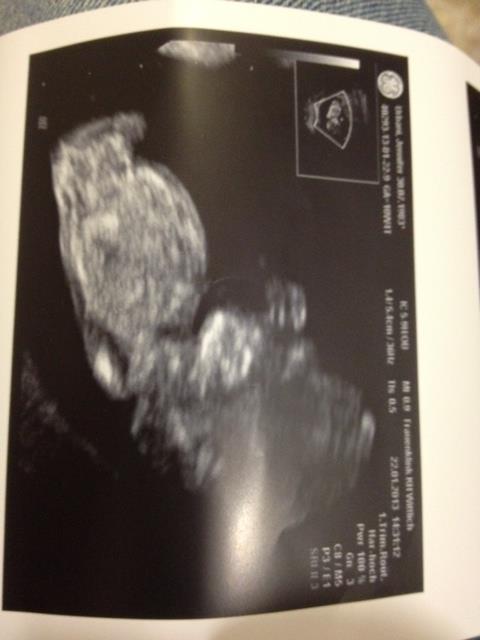

She's 12 weeks.

I guess girl :)

Thanks. I was thinking girl too.

What makes you guys say girl? I am actually leaning boy......although I'm not sure a nub is visible.

I don't see a nub.

I can't quite see the nub...looks like bub is twisted?